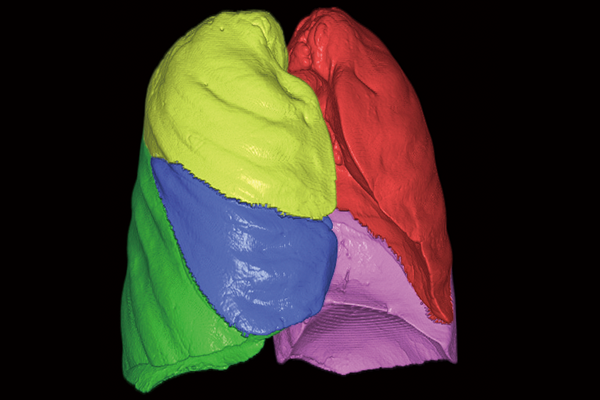

SYNAPSE 3D’s advanced image analysis technology aids clinical interpretation, reporting, and treatment planning. Especially, automatic organ segmentation technology enables fast and effective workflow, powered by REiLI, FUJIFILM's AI brand. With a series of high-tech applications developed in collaboration with clinical specialists, SYNAPSE 3D quickly and accurately delivers imaging result that promotes effective care collaboration.

REiLI makes it happen to extract organs and simplify your work.

Lung lobe

Liver

Kidney

Colon

Lung Analysis

Virtual Endoscope

Orthopedics